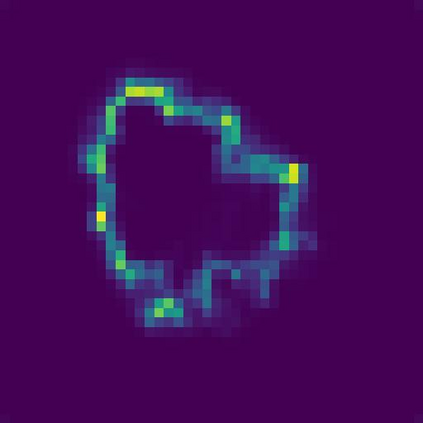

Skin lesion segmentation from dermoscopy images is of great significance in the quantitative analysis of skin cancers, which is yet challenging even for dermatologists due to the inherent issues, i.e., considerable size, shape and color variation, and ambiguous boundaries. Recent vision transformers have shown promising performance in handling the variation through global context modeling. Still, they have not thoroughly solved the problem of ambiguous boundaries as they ignore the complementary usage of the boundary knowledge and global contexts. In this paper, we propose a novel cross-scale boundary-aware transformer, \textbf{XBound-Former}, to simultaneously address the variation and boundary problems of skin lesion segmentation. XBound-Former is a purely attention-based network and catches boundary knowledge via three specially designed learners. We evaluate the model on two skin lesion datasets, ISIC-2016\&PH$^2$ and ISIC-2018, where our model consistently outperforms other convolution- and transformer-based models, especially on the boundary-wise metrics. We extensively verify the generalization ability of polyp lesion segmentation that has similar characteristics, and our model can also yield significant improvement compared to the latest models.